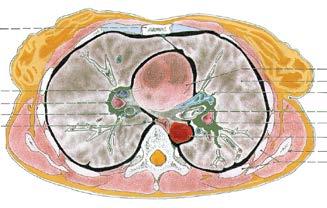

Obr. 10. TVAR SRDEČNíCH KOMOR na příčném řezu srdcem

A SRDCE; pohled zezadu; naznačena rovina příčného řezu komorami

B TVAR A TLOUŠŤKA STĚN SRDEČNíCH KOMOR v rovině řezu na obr. A; pohled zprava shora zezadu doleva dolů dopředu, ve směru srdeční osy

a) Na základě rozdílů velkého a malého oběhu krevního: